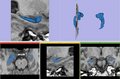

• Segmentation of the hippocampus using a multi-scale shape based method.

We represent and learn the shape in a multi-scale method and then perform the segmentation of the hippocampus.

The code has been written and the method is being tested on multiple data sets.